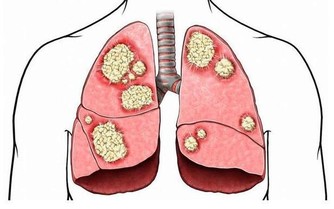

在大多數人眼裡,以為血管擁堵是只發生在老年人身上的事情。其實不然,人過了30歲後,血管板塊就加速變大了。如果將心血管比作水管,血液中的膽固醇、甘油三酯等類似「水垢」,堆積在血管壁上越多,形成如同黃色小米粥樣的斑塊,容易阻塞血管。

如果放著不管,有些養分和氧氣不能有效到達周邊細胞,就會面臨細胞死亡,而且血液粘稠容易引起血管擁堵,但剛開始發作的時候,並沒有什麼明顯標誌的信號,很容易造成大家的忽視,一般輕者會有頭暈,容易忘東西,腰疼長斑皺紋,失眠,體寒等症狀,嚴重的就會出現動脈硬化,引起心肌梗塞,甚至還會引起腦中風現象。